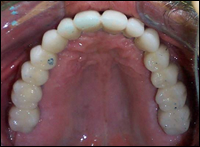

Fig 8 & 9: 14 unit porcelain fused to metal bridges were cemented in place. These prostheses look and fell as close to natural teeth as possible. There is no bulky denture material covering the gums or palate.